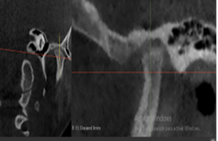

Plan de tratamiento: Debido a todo lo expuesto se decidió colocar un aparato de avance mandibular tipo monoblock para recapturar el disco. Para ello se inició con la realización de una mordida constructiva para la confección del aparato, se llevó a una coincidencia de las líneas media y un adelantamiento mandibular de 3 mm (Figuras D, E y F). Posteriormente se envió los registros para la confección del dispositivo de avance mandibular tipo monoblock (Klammt Clase II) que fue instalado en marzo del 2023 constatando de que se encuentre totalmente adaptado (G), las indicaciones de uso fueron más de 20 horas al día aconsejando que la paciente se lo retire únicamente para comer y para el aseo respectivo. Los controles se realizaron a las 2 semanas y después con una frecuencia mensual durante 12 meses.

Se prescribió un nuevo examen tomográfico en el que se pudo constatar que se cumplió el objetivo de tratamiento, ya que se consiguió la descompresión de la zona retrodiscal dando lugar a la formación de un pseudodisco que compensó el adelantamiento discal bilateral existente.

Se pudo observar en la imagen tomográfica (Figura 4) la ATM derecha la neoformación de tejido óseo con una ligera erosión en la zona anterior del cóndilo mandibular (A), mientras que en la ATM izquierda se visualizó la formación de un osteofito el cual se genera en etapas avanzadas durante un cambio degenerativo a más de la formación de tejido óseo (B).